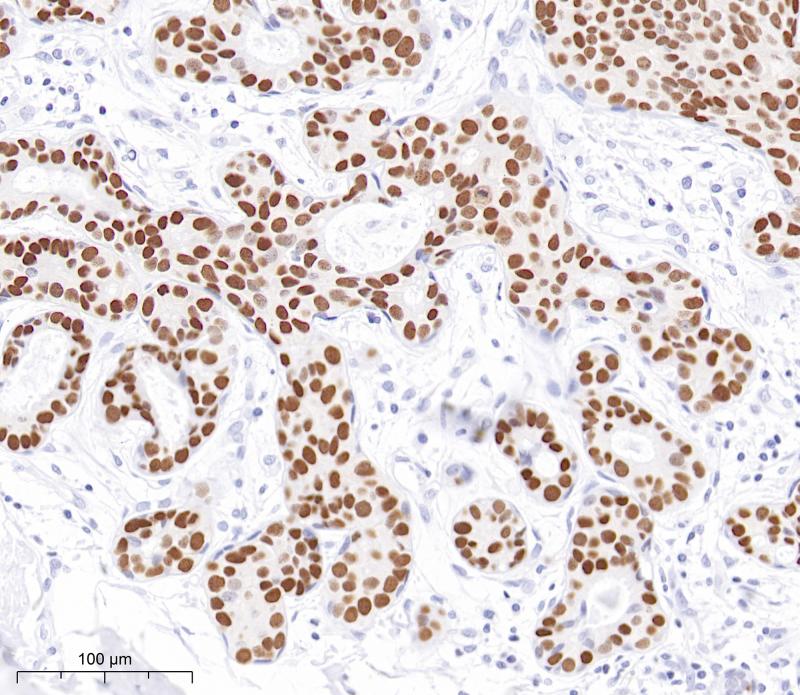

角化蛋白是一种典型的上皮中间纤维蛋白,显示出显著的分子多样性。杂聚纤维是由I型和II型分子配对形成的。在人类中存在54个功能性角蛋白基因。它们在上皮细胞和细胞分化阶段表示出高度特异性地表达。这种抗体可以检测高分子量的CK10、CK14、CK15和CK16,以及低分子量的CK19。它通常和II型细胞角蛋白抗体形成细胞角蛋白鸡尾酒使用。

阳性对照

宫颈癌

亚细胞定位

细胞质